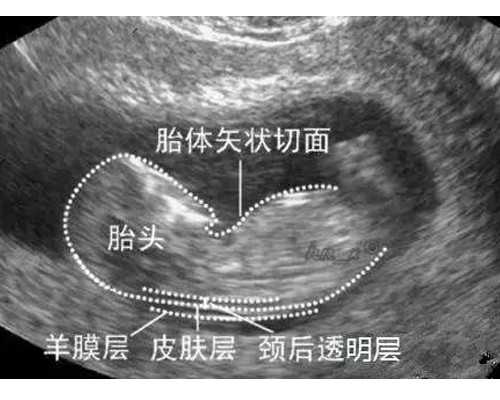

(3)在月经周期后的第2-3天,检测女性基础性激素,并进行盆腔B超检查、阴道分泌物检查;必要时,还要进行子宫内膜活检、宫颈细胞学检查。